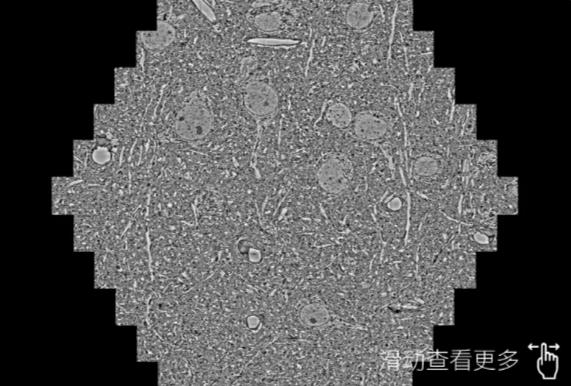

鼠脑切片。左图使用船营蔡司船营扫描电镜MultiSEM706对165μmx143pm面积区域成像,耗时仅需1.5秒。右图为鼠脑切片中30μm区域放大效果。样品由芝加哥大学B.Kasthuri提供。

使用蔡司高速船营扫描电镜MultiSEM对1mm²人脑皮层组织进行高分辨成像,并对其中的各种细胞结构进行三维重构分析。左图展示了2x3mm²组织平面中锥体神经元的三维重构效果。右图显示了局部体积神经元三维重构。图像由哈佛大学chtman实验室提供,渲染图由D. Berger 制作。